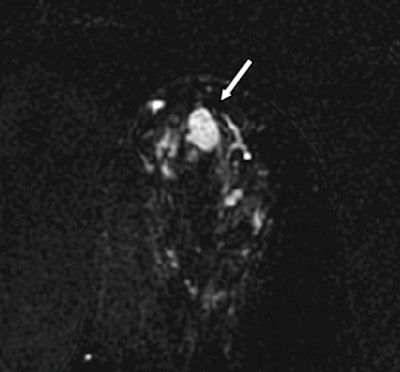

![]() |

| The lesion (arrow) is hyperintense on axial DWI (above) and has a low ADC on an ADC map (below). No evidence of carcinoma was detected at excisional biopsy. |